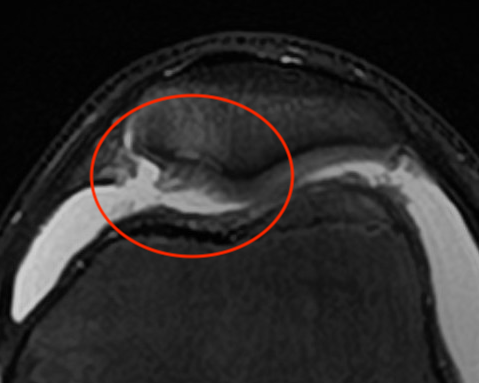

MRI

- patella tilt / Lateral patella pressure syndrome